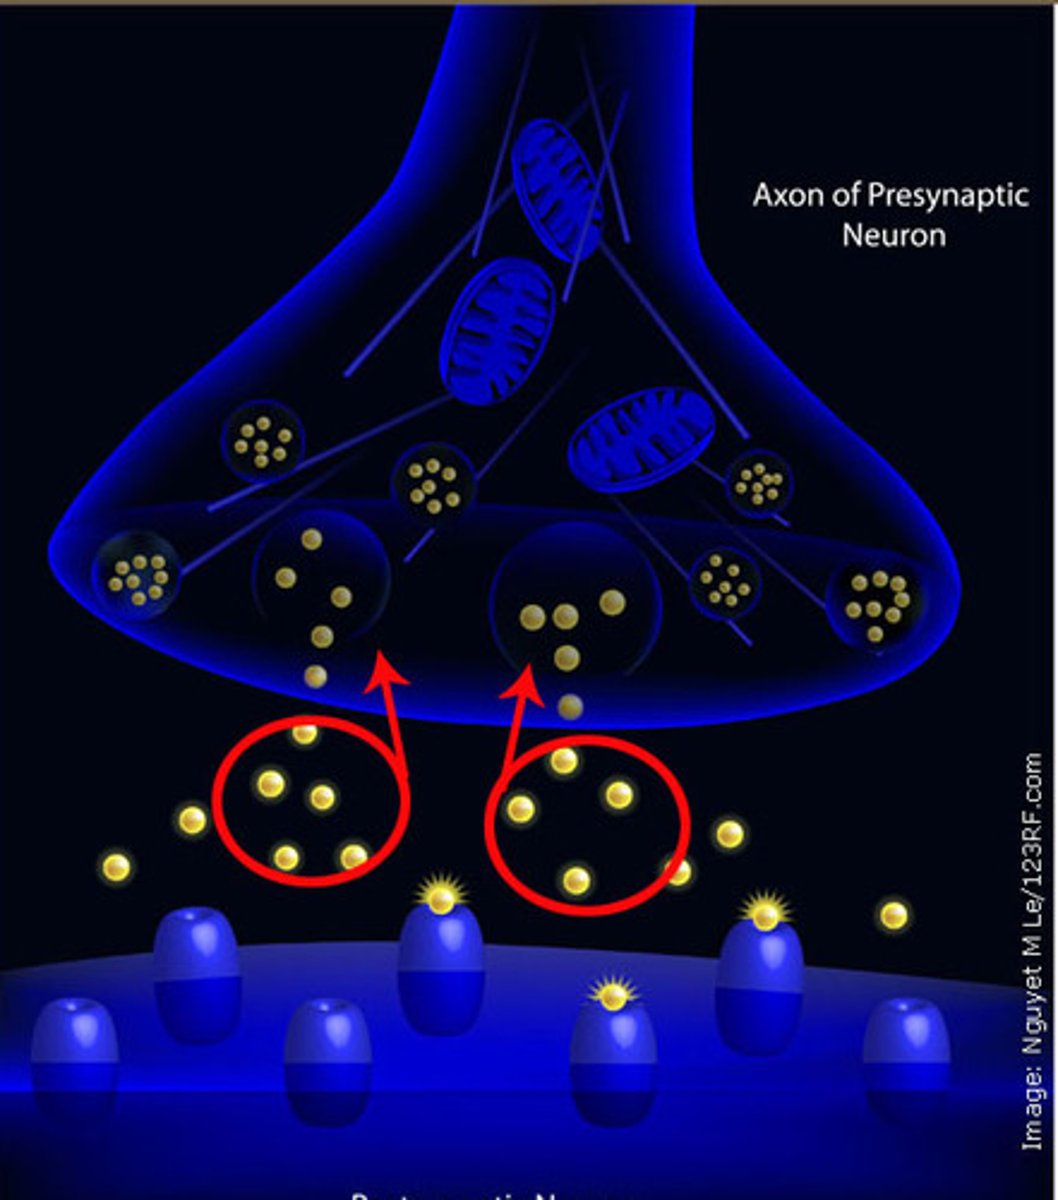

Reuptake

reabsorption of a neurotransmitter by the sending neuron after it completes its work

All-or-nothing principle

a neuron can release all of its neurotransmitters or none

Antagonists

bind to receptors and block a neurotransmitter's functioning

Agonists

these mimic a neurotransmitter and stimulate an action (e.g., morphine mimics endorphins)

Reuptake inhibitors

drugs that interfere with the reabsorption of neurotransmitters in the synapse so that a greater amount remains in the synapse